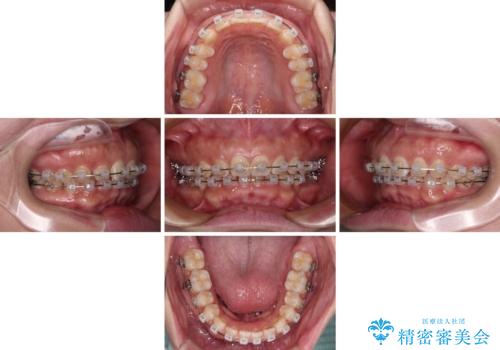

【モニター】ディープバイトを治す ワイヤー装置による矯正治療

- クリアブラケット

- 2年1ヶ月

- 顎が疲れるほどのディープバイトを気にして来院された患者様です。

手前に傾斜している奥歯を直立させながら、歯列全体の平面を均一に整えることでディープバイトを改善していくこととしました。

ディープバイトは咬合力が強いことが特徴であり、より良い仕上がりとするために、臼歯部のコントロールを行いやすいワイヤー装置を用いて矯正治療を行うこととしました。